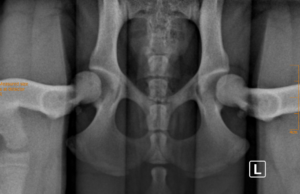

After some discussion of options it was deemed necessary to take some radiographs of her hips to check for signs of laxity or anything that could be causing discomfort before considering behavioural causes.

Lola was booked in for a procedure call “PennHip” radiographs. PennHip is a hip screening procedure developed by the University of Pensylvania. The radiographs are assessed and compared to a comprehensive medical database and indicate the individual animals risk of developing osteoarthritis from Canine Hip Dysplasia. The radiographs can be used as a screening tool in animals as young as 14 weeks to screen for risk and allow early intervention (Keep your eyes out for a story on Dr. Jaimie’s own pup Doug and his story!).

Dr Jenny performed Lola’s PennHIP radiographs and when we received the report it was found she has significant laxity in both hips- and was likely suffering already due to her conformation! Her pain was managed with oral medications and the fly biting resolved straight away!

Due to the extent of her issues the surgical specialist at SASH Kent Town was consulted. They advised that she was an excellent candidate for a specialist surgical procedure called a Double Pelvic Osteotomy for both of her hips. The goal of this surgery is to improve the fit of the head of the femur (ball) into the acetabulum (socket).